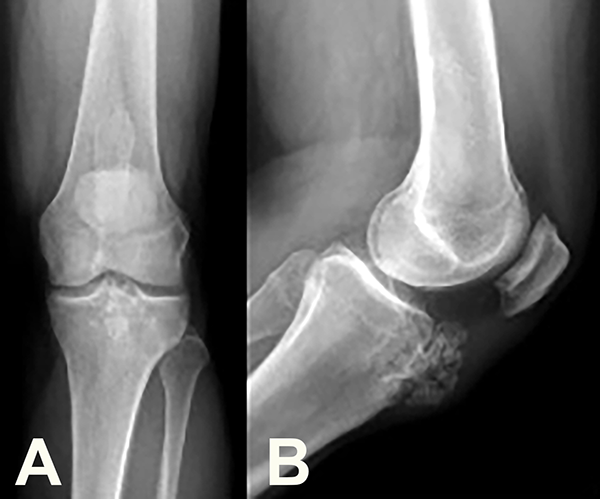

En las radiografías (Rx) se observó una tumoración vellosa con múltiples calcificaciones sobre la TAT, edema y engrosamiento del tendón rotuliano (TR). Se advirtió, además, una imagen esclerosa medular de bordes netos en la región metafiso-diafisaria distal del fémur (fig. 2).

Figura 2: Radiografía de frente (2a) y perfil (2b). Véase la tumoración a nivel anterior de la TAT con múltiples calcificaciones. Imagen en canal medular del fémur con bordes escleróticos.